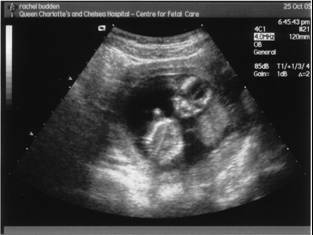

Hmm, okay, so this is more like monthly but things are really hotting up now. We've had the first scan and it looks like everything is going according to the extraordinary program we coded in a few months ago. Hopefully the data wasn't corrupt and the hardware seems to be in good condition. In fact, it looks like this:

This was the most amazing part of the process so far. The pictures are grainy and hard to understand but when seen in action - and it looks like Buddy is going to be just as restless and fidgety as his / her mother - the eyes and brain fill in a lot of information using the movements and 'edges' of the baby. They allow you to interpret a very vivid picture full of detail, and unexpectedly developed. Please note, I'm not claiming that our child is already "very advanced for its age" but it was a week older than we thought so we saw the little fingers moving about, saw the heart beating and the twin lobes of its brain were easy to spot too, looking like a cross-section through a tiny cauliflower. I had a great view, unlike Rach who was pushed back by the doctor every time she leaned up, which I hardly realised as I was staring too hard at the screen. It's pretty easy to get carried away at this stage because on a big screen the baby looks so much larger than it really is but this was the first bit of magic. Hopefully Rach will get a better view when we go back for the second scan at 20 weeks.

I had a prolonged showing too, which felt like a real privilege, because the baby was sitting upright (probably reading or something) and wouldn't get into a good position for the doc to measure the back of its neck (part of the screening for Downs Syndrome). I'd say stubborn like its mother (and me to be entirely fair) but having seen its brain being about the size of a thumbnail, elegant, symmetrical and vegetable-y, I wouldn't impute to much higher function characteristics to it just yet.

PS Although marvellous, at this stage Buddy bears more than a passing resemblance to 80's Eagle character Doomlord. For comparison, and pray it isn't true…..

Buddy